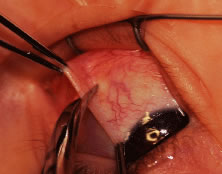

Another common source of hemorrhage is bleeding from the anterior ciliary vessels. This bleeding may occur when a needle is passed through the tendon and penetrates one of the anterior ciliary vessels. This penetration will cause a self-limited hematoma under the muscle capsule (Fig. 75). It may also occur when the Tenon's tissue is cleaned from the muscle (Fig. 76). Hemorrhage around the insertion may make removal of the muscle from the globe difficult because it can obscure the area where the tendon of the muscle is attached to the globe. Bleeding from the anterior ciliary vessels can be controlled by cauterizing vessels with a wet-field (bipolar) cautery. Care should be taken not to cauterize tissue near a suture after it has been placed because doing so may cause structural damage to the suture.

Fig. 75. A small hematoma in the muscle capsule resulted from cutting the anterior ciliary vessel when cleaning the muscle insertion before placing the suture.

Fig. 76. The muscle capsule has been removed from the muscle tendon. Hemorrhage can occur, which can obscure the surgical field.